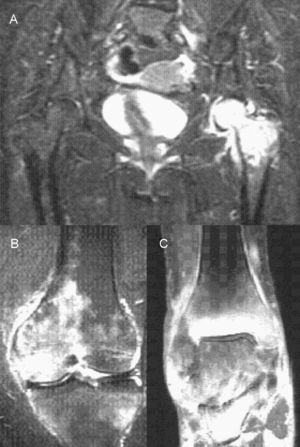

Se trató con reposo en cama, analgésicos, antiinflamatorios, corticoides y neuromoduladores, y se practicó una infiltración corticoanestésica en el trocánter mayor que no fue efectiva. La gammagrafía ósea mostró hipercaptación grave en la articulación coxofemoral, la cabeza femoral y la región trocanterea indicativa de osteonecrosis (fig. 1). Las analíticas de sangre y de orina fueron normales. La resonancia magnética (RM) de cadera mostró extenso cambio de señal en la cabeza, el cuello y la metáfisis femoral, hipointenso en T1 e hiperintenso en T2, y derrame articular compatible con osteoporosis transitoria de cadera (fig. 2). A los 12 días se la dio de alta con tratamiento (antiinflamatorio, calcio, vitamina D y calcitonina nasal). Se autorizó la movilización de la cadera, pero no la carga.

A las 24 semanas el dolor de cadera y lumbar había disminuido mucho, pero explicaba el dolor en la rodilla izquierda intenso referido a interlínea interna; la radiografía era normal. A las 26 semanas además refería dolor en el tobillo derecho referido a maleolo interno; la radiografía también era normal. La RM de rodilla mostró degeneración del cuerno posterior del menisco interno, inflamación del ligamento lateral interno, marcados cambios de señal en el cóndilo femoral interno, la meseta tibial externa y la cabeza peroneal compatibles con focos de edema-contusión ósea, y pérdida de volumen del cartílago articular patelar (fig. 2). Una segunda gammagrafía mostró hipercaptación grave del tobillo derecho indicativa de osteocondritis u osteonecrosis, hipercaptación moderada–grave del cóndilo femoral interno de la rodilla izquierda indicativa de osteocondritis e hipercaptación de la cabeza femoral izquierda disminuida con respecto a la gammagrafía previa (fig. 1). Se le diagnosticó osteoporosis transitoria migratoria.

A las 34 semanas refería dolor de la rodilla izquierda ocasional, pero dolor del tobillo derecho intenso. A las 39 semanas explicaba dolor del tobillo derecho muy intenso con signos inflamatorios, cojera importante e impotencia funcional grave, caminaba con 2 bastones. La RM de tobillo mostró un proceso inflamatorio extenso preferentemente en el maleolo tibial con afectación leve de la cúpula astragalina, artropatía degenerativa tibioastragalina, marcado edema difuso de partes blandas, osteoporosis parcheada que afectaba al astrágalo, a los escafoides y la cuña, y atrofia muscular (fig. 2). Solicitamos rehabilitación funcional. A las 52 semanas, tras una mejoría del dolor del tobillo, éste volvió a aumentar y se añadió un bifosfonato oral semanal.